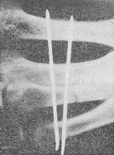

![]() Рис. 12. Перелом діафізу IV п'ясткової кістки (стан після операції) |

В останні роки широке застосування отримує трансоссальная фіксація п'ясткових кісток однією або двома металевими спицями ЦІТО (рис. 12).